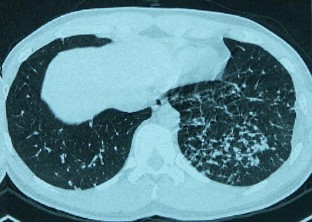

Takayasu’s arteritis presenting with bilateral pulmonary granulomatosis

Takayasu’s arteritis (TA) is a vasculitis characterized by inflammation and obliteration of intermediate to large-size arteries. We report a case of Takayasu’s arteritis with a presentation of bilateral pulmonary nodular infiltrates in a 21-year-old man. An open-lung biopsy showed characteristic changes of extra-vascular granulomatosis. To our knowledge, this has not been described previously in the literature.

Fig. 1